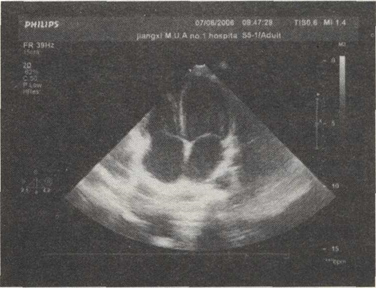

7.如图,该切面为哪种超声心动图切面()